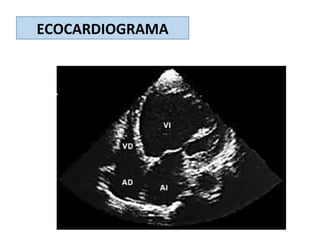

ECOCARDIOGRAMA

VENTRICULOGRAFIA ISOTÓPICA

estudiar los diámetros y

función ventricular, sistólica y

diastólica, y la presencia de

alteraciones en la motilidad

regional, siendo

particularmente útil en casos

con mala ventana

ecocardiográfica